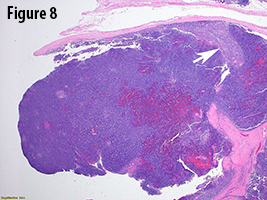

In the current case, gross evaluation (Figure 2) reveals a fleshy, lobulated, tan-pink solid and focally cystic mass with adjacent thymus tissue. Low power microscopic evaluation (Figure 8) shows a dense lymphoid infiltrate with a fibrous capsule and hypocellular fibrous septa. Also in figure 8, an area of paler tissue (arrow), a so-called “medullary island”, is identified along with Hassall corpuscles (Figure 9 arrow). Figure 10 shows scattered epithelioid cells (arrows). These morphologic features are consistent with a WHO type B1 thymoma.